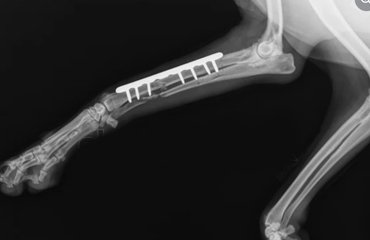

We are the only orthopedic specialty veterinary clinic in Dubai, located in Arjan. We specialize in advanced surgical procedures for dogs and cats. Our mission is to diagnose and treat a wide range of musculoskeletal conditions helping pets restore their mobility, comfort, and quality of life.

Our team of veterinary specialists encompasses extensive experience in almost all areas of animal surgeries, including advanced soft tissue and orthopedic surgeries, and neurosurgery. By utilizing advanced diagnostic and therapeutic equipment, our specialists work together to deliver individualized care for your pet.